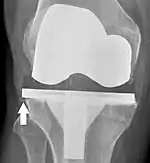

El aflojamiento de la prótesis puede estar indicado en la radiografía por espacios radiotransparentes delgados alrededor del implante, o más obviamente por el desplazamiento del implante.[48]

El reemplazo de rodilla se evalúa de forma rutinaria mediante rayos X, incluidas las siguientes medidas: